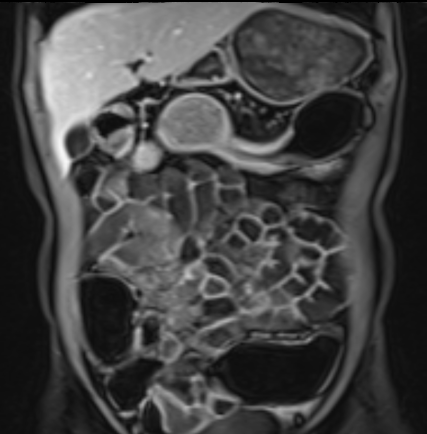

Hẹp lòng ruột

Hẹp lòng ruột có thể biểu hiện bằng hình ảnh thành ruột dày kết hợp với lòng ruột bị thu hẹp.

Sự hiện diện của giãn ruột trước chỗ hẹp làm tăng khả năng chẩn đoán hẹp lòng ruột.

Ngấm thuốc tương phản bất thường của đoạn ruột bị ảnh hưởng thường hiện diện.

Trong hệ thống phân độ, chỉ hẹp nặng mới được xếp vào nhóm biến chứng, được định nghĩa là hẹp có giãn ruột trước chỗ hẹp và tín hiệu T2W thành ruột tăng mức độ vừa đến rõ rệt.

Hình ảnh thu hẹp lòng ruột có thể do co thắt gây ra, vì vậy cần kiểm tra các chuỗi xung khác trước khi đưa ra chẩn đoán hẹp lòng ruột.

Ruột non bình thường, nhưng ghi nhận các đoạn hẹp ở đại tràng xuống và đại tràng ngang.

Cả hai đoạn hẹp đều có thành ruột dày đến 8 mm và ngấm thuốc rõ rệt theo kiểu niêm mạc ở đại tràng xuống và kiểu phân lớp ở đại tràng ngang.

Giãn ruột trước chỗ hẹp được ghi nhận ở cả hai đoạn.